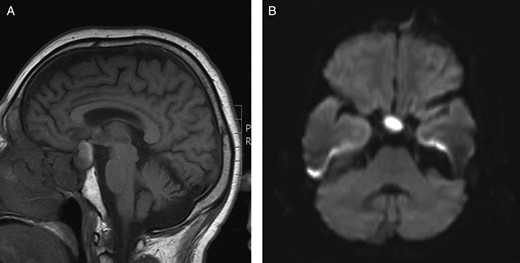

(A) Preoperative sagittal T1-weighted MRI showing a predominantly isointense lesion in the pituitary fossa with some high signal posteriorly. (B) Preoperative axial diffusion-weighted MRI demonstrating a hyperintense lesion in the pituitary fossa.

Unfortunately, MRI is not specific in identifying pituitary abscess as the signal intensity of an abscess may be affected by its protein content or the presence of haemorrhage. MRI may demonstrate a pituitary abscess as a generally homogenous cystic lesion, typically hyperintense on T2-weighted images and isointense on T1-weighted images, surrounded by a ring of contrast enhancement, although this appearance is variable [6]. Some pituitary abscesses may also show high signal intensity on diffusion-weighted MRI [5]. Other sellar lesions which may exhibit a restriction of diffusion on MRI include macroadenomata, apoplexy and autoimmune hypophysitis. Although restricted diffusion was demonstrated in our case (Fig. 1B), the ambiguous clinical and radiological features focused our preoperative suspicions on commoner pathology (i.e. a macroadenoma). While autoimmune hypophysitis may present clinically and radiologically in a similar fashion, the characteristic histopathological finding of lymphocytic infiltration within pituitary tissue was absent. Although not apparent in our case, secondary pituitary abscesses may share radiological characteristics with the lesions from which they arise [6].